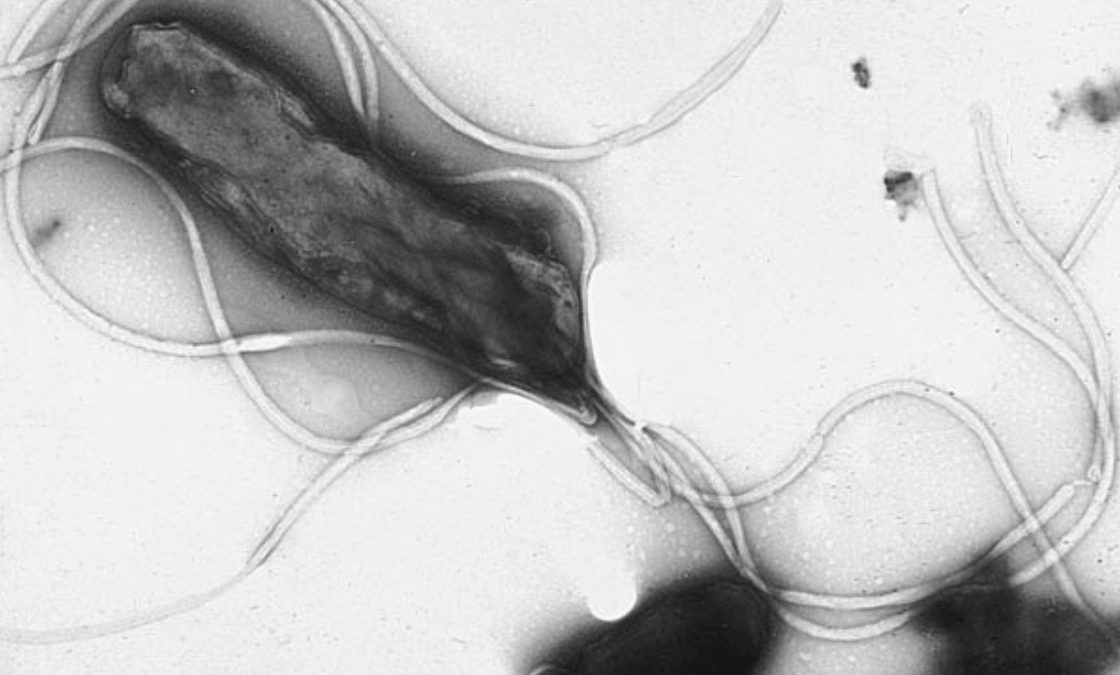

Helicobacter pylori visto al microscopio electrónico. | Wikipedia